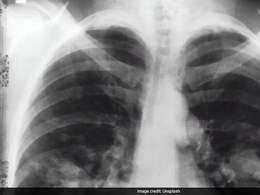

Pulmonary Embolism

While DVT is a serious condition by itself, the most dangerous complication comes when a clot travels to the lungs, resulting in a pulmonary embolism (PE)